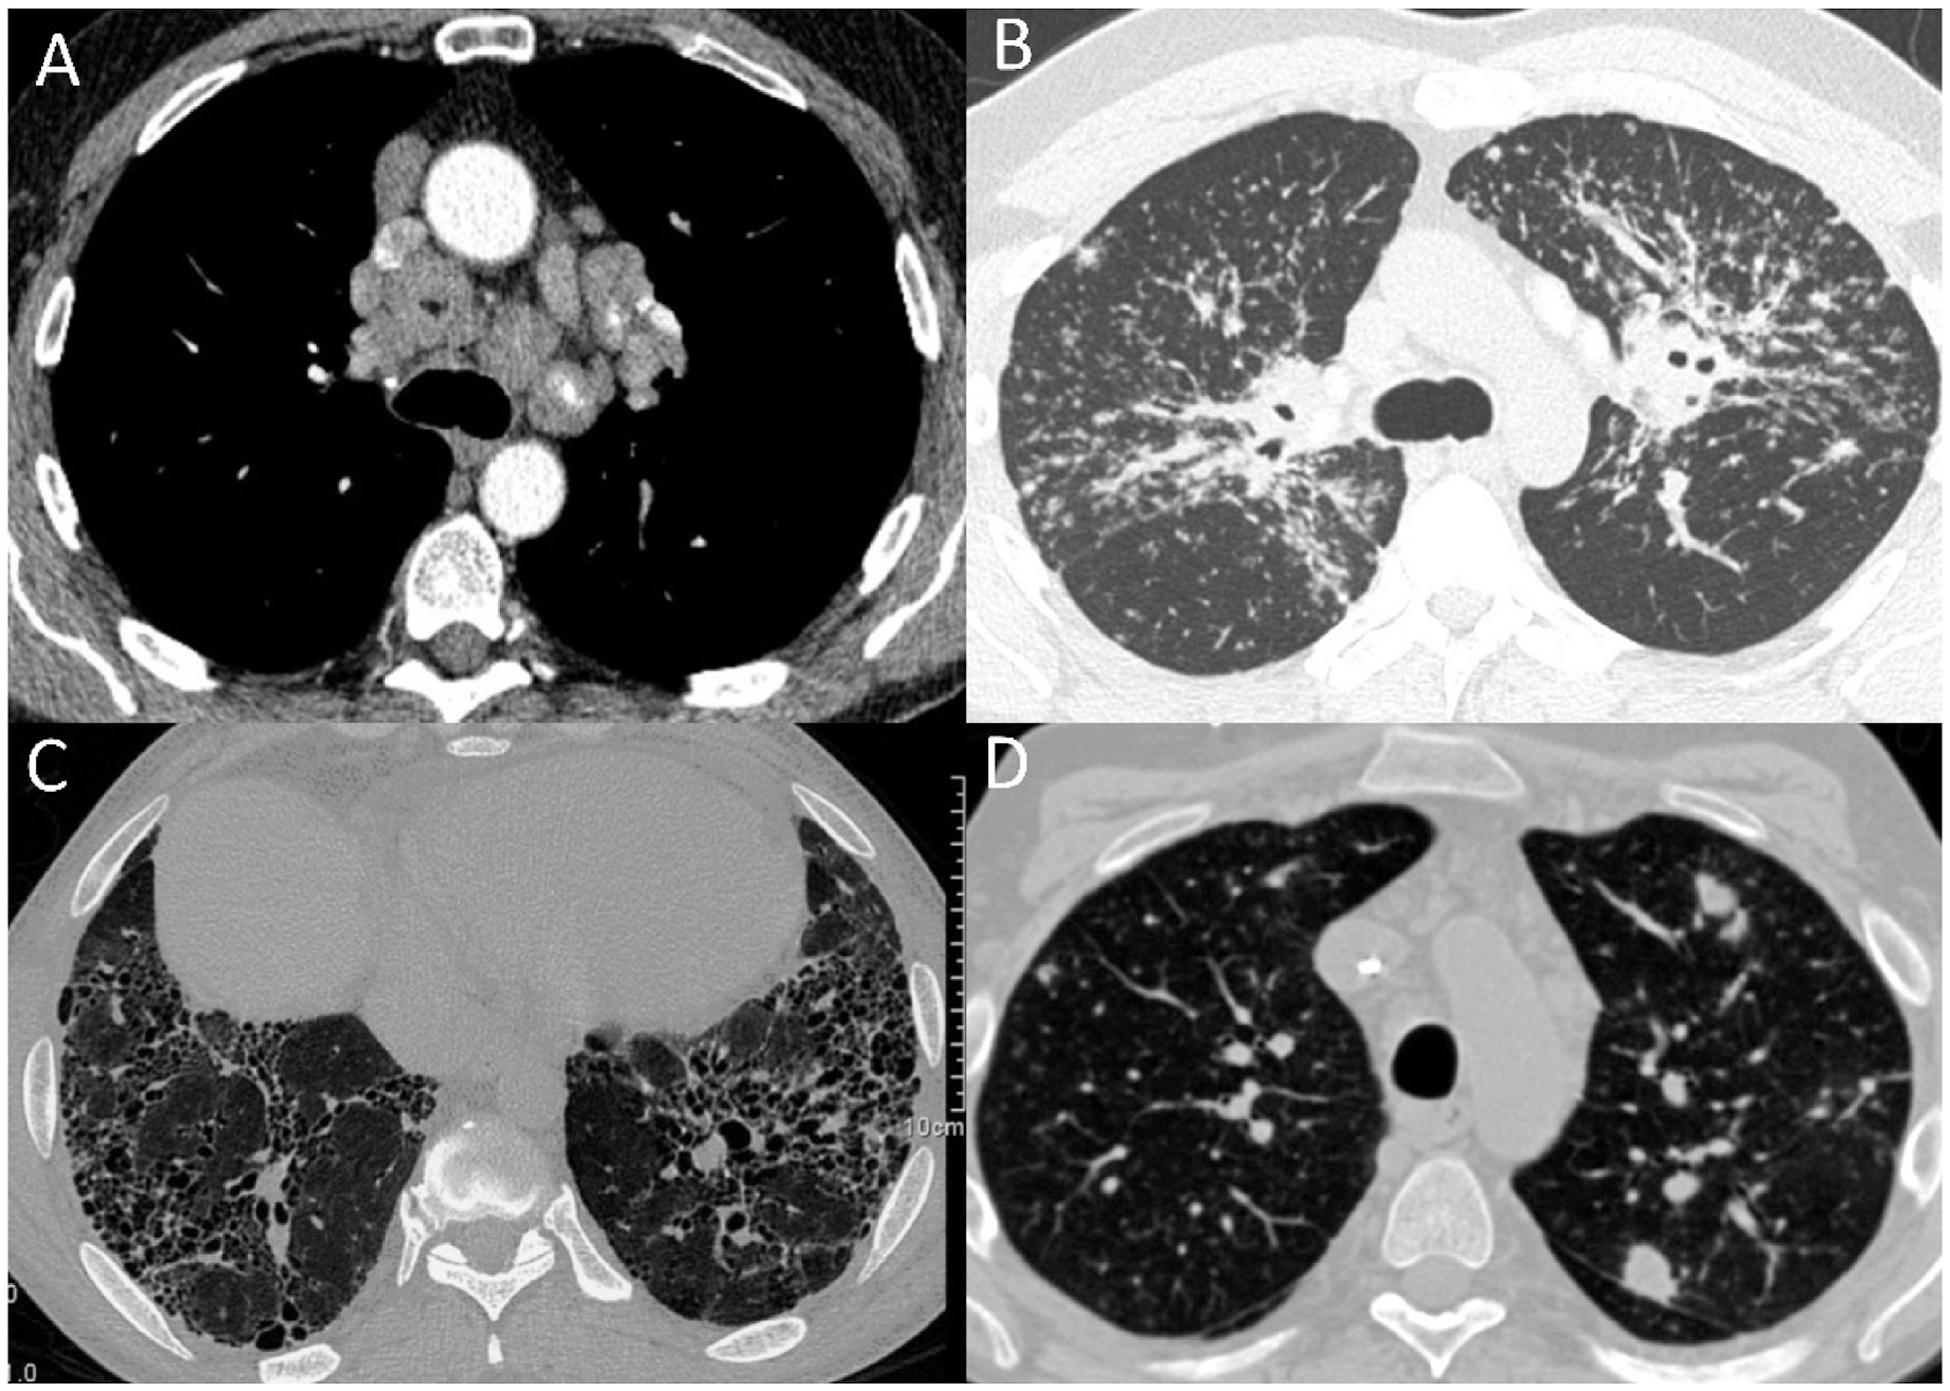

A framework for exclusion of alternative diagnoses in sarcoidosis.

Sarcoidosis is a multisystem granulomatous syndrome that arises from a persistent immune response to a triggering antigen(s). There is no "gold standard" test or algorithm for the diagnosis of sarcoidosis, making the diagnosis one of exclusion. The presentation of the disease varies substantially between individuals, in both the number of organs involved, and the manifestations seen in individual organs. These qualities dictate that health care providers diagnosing sarcoidosis must consider a wide range of possible alternative diagnoses, from across a range of presentations and medical specialties (infectious, inflammatory, cardiac, neurologic). Current guideline-based diagnosis of sarcoidosis recommends fulfillment of three criteria: 1) compatible clinical presentation and/or imaging 2) demonstration of granulomatous inflammation by biopsy (when possible) and, 3) exclusion of alternative causes, but do not provide guidance on standardized strategies for exclusion of alternative diagnoses. In this review, we provide a summary of the most common differential diagnoses for sarcoidosis involvement of lung, eye, skin, central nervous system, heart, liver, and kidney. We then propose a framework for testing to exclude alternative diagnoses based on pretest probability of sarcoidosis, defined as high (typical findings with sarcoidosis involvement confirmed in another organ), moderate (typical findings in a single organ), or low (atypical/findings suggesting of an alternative diagnosis). This work highlights the need for informed and careful exclusion of alternative diagnoses in sarcoidosis.

结节病是一种多系统肉芽肿综合征,由对触发抗原的持续免疫反应引起。目前尚无诊断结节病的“金标准”检测方法或诊断流程,这使得结节病的诊断成为一种排除性诊断。该疾病在个体之间的表现差异很大,涉及的器官数量以及单个器官的表现均有所不同。这些特点决定了诊断结节病的医疗保健人员必须考虑一系列可能的替代诊断,涵盖各种表现形式和医学专业领域(感染性、炎症性、心脏、神经)。目前基于指南的结节病诊断建议满足三个标准:1)临床表现和/或影像学表现相符;2)通过活检(如有可能)证实存在肉芽肿性炎症;3)排除其他病因,但未提供排除替代诊断的标准化策略指导。在本综述中,我们总结了结节病累及肺、眼、皮肤、中枢神经系统、心脏、肝脏和肾脏时最常见的鉴别诊断。然后,我们基于结节病的验前概率提出了一个用于排除替代诊断的检测框架,验前概率分为高(在另一器官已证实有结节病累及的典型表现)、中(单个器官的典型表现)或低(非典型/提示替代诊断的表现)。这项工作强调了在结节病诊断中明智且谨慎地排除替代诊断的必要性。